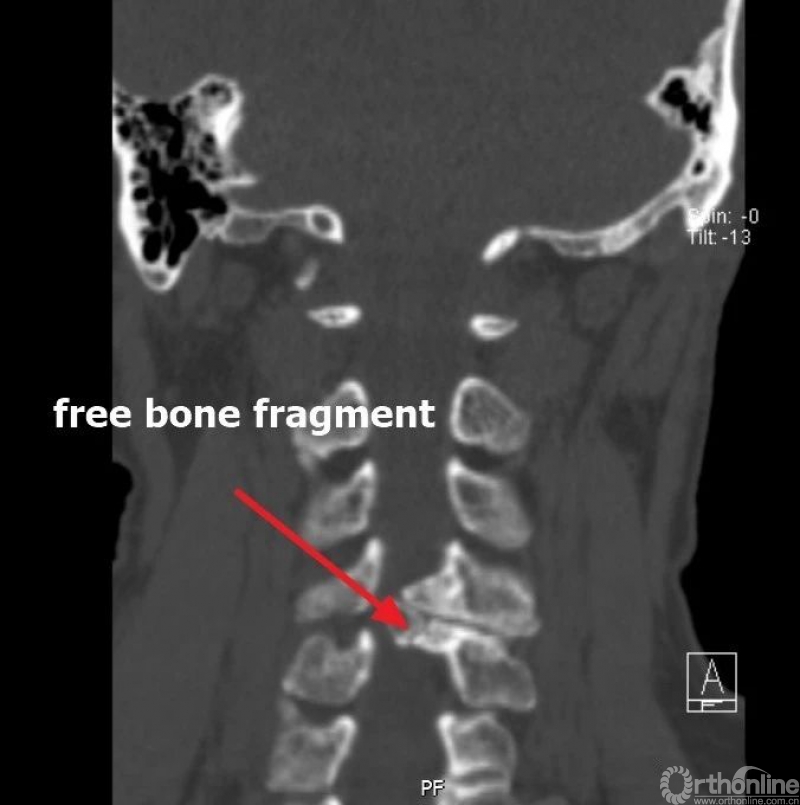

入院查体患者四肢肌张力高,双侧hoffman阳性。CT及MRI检查提示C4/5左侧关节突内缘有一巨大骨块(15mm*16mm),相应节段椎管严重狭窄。椎管内骨块的前端还有一游离骨块。

影像学资料